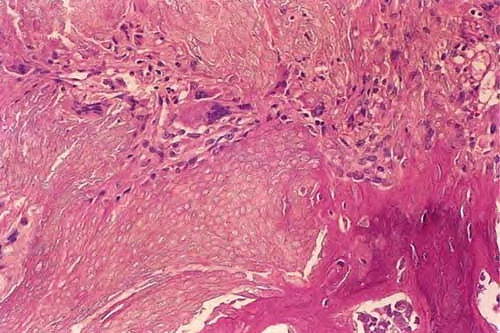

Pilomatricoma shows a spectrum of morphologic features that mainly reflect different evolutionary stages. Early and well-developed pilomatricomas reveal variably sized, round to oval cystic lesions lined by a basaloid epithelium at the periphery and filled in the center with masses of eosinophilic, faulty hair matrix material containing “shadow” (“ghost”) cells

Basaloid (matrical) cells show monomorphous round nuclei with one or more distinctive nucleoli and variable numbers of mitotic figures. Foci of squamoid epithelium are sometimes noted within the epithelial lining. Regressing pilomatricomas display haphazardly arranged foci of basaloid cells and shadow cells as well as an inflammatory infiltrate with multinucleated histiocytic giant cells. Granulation tissue is sometimes noted. Old pilomatricomas reveal no basaloid component but show irregularly shaped, partially confluent masses of shadow cells with foci of calcification or ossification. Melanin deposition, trans-epidermal elimination, and extramedullary hematopoiesis have been described in some pilomatricomas. A peculiar variant with relatively large areas of basaloid cells and small foci of shadow cells (“proliferating pilomatricoma”) is occasionally observed in older adults.